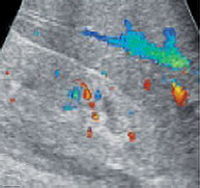

При проведении пробы Зимницкого выявляется изогипостенурия. УЗИ почек свидетельствует о снижении толщины паренхимы и уменьшении размера почек. Снижение внутриорганного и магистрального почечного кровотока выявляется на УЗДГ сосудов почек. Рентгенконтрастную урографию следует применять с осторожностью из-за нефротоксичности многих контрастных препаратов. Перечень других диагностических процедур определяется характером патологии, ставшей причиной развития ХПН.